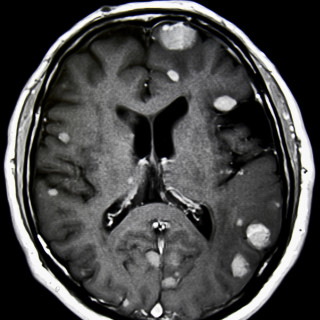

Bildet viser leukemiske hudinfiltrasjoner hos en mann i 50-årene diagnostisert med akutt myelogen leukemi. Pasienten ble overført fra lokalsykehus til hematologisk avdeling ved universitetssykehus, der han ble innlagt med spørsmål om alvorlig infeksjon. Han hadde da 14 dagers sykehistorie med tiltakende luftveissymptomer, økende dyspné og fallerende allmenntilstand. De siste fire dagene var det også tilkommet flere flekkvise, nodulære hudlesjoner, mest uttalt på hals, bryst og overekstremiteter. Blodprøver ved ankomst universitetssykehuset viste hemoglobin 8,1 g/dL (referanseområde 13,4–17,0)...